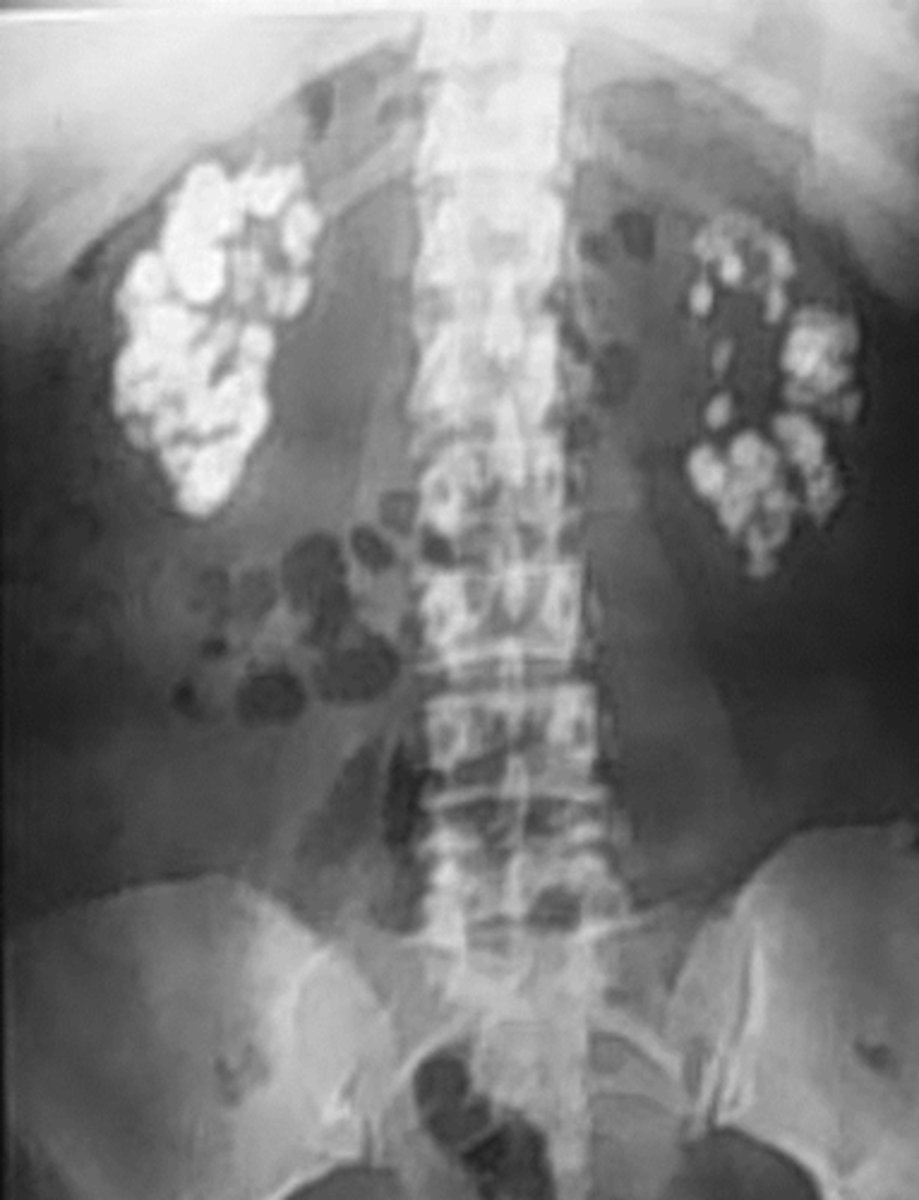

etiology of most calcifications can be determined by evaluatin

anatomic location, pattern of calcification

Lamellar "laminated" pattern

amorphous "popcorn" calculi

porcelain gallbladder